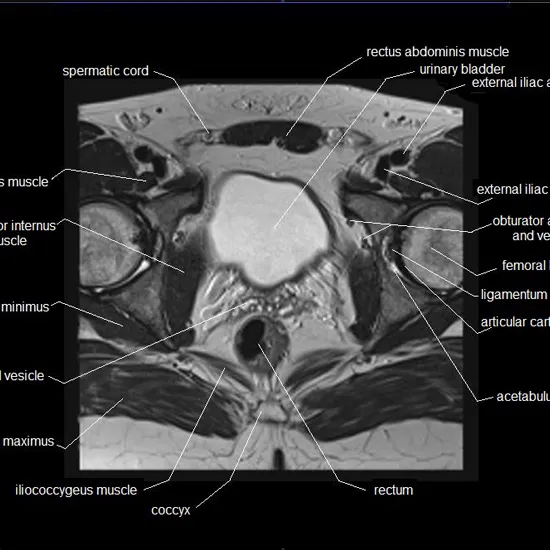

The magnetic resonance imaging of the upper pelvic region gets images of organs, bones, blood vessels and other areas around it.

This MRI examination captures images throughout your pelvic region using magnetic and radiofrequency without requiring a surgical incision. This scan helps your physician to see your body's soft tissues, such as tendons and organs, without your bones hindering your vision.